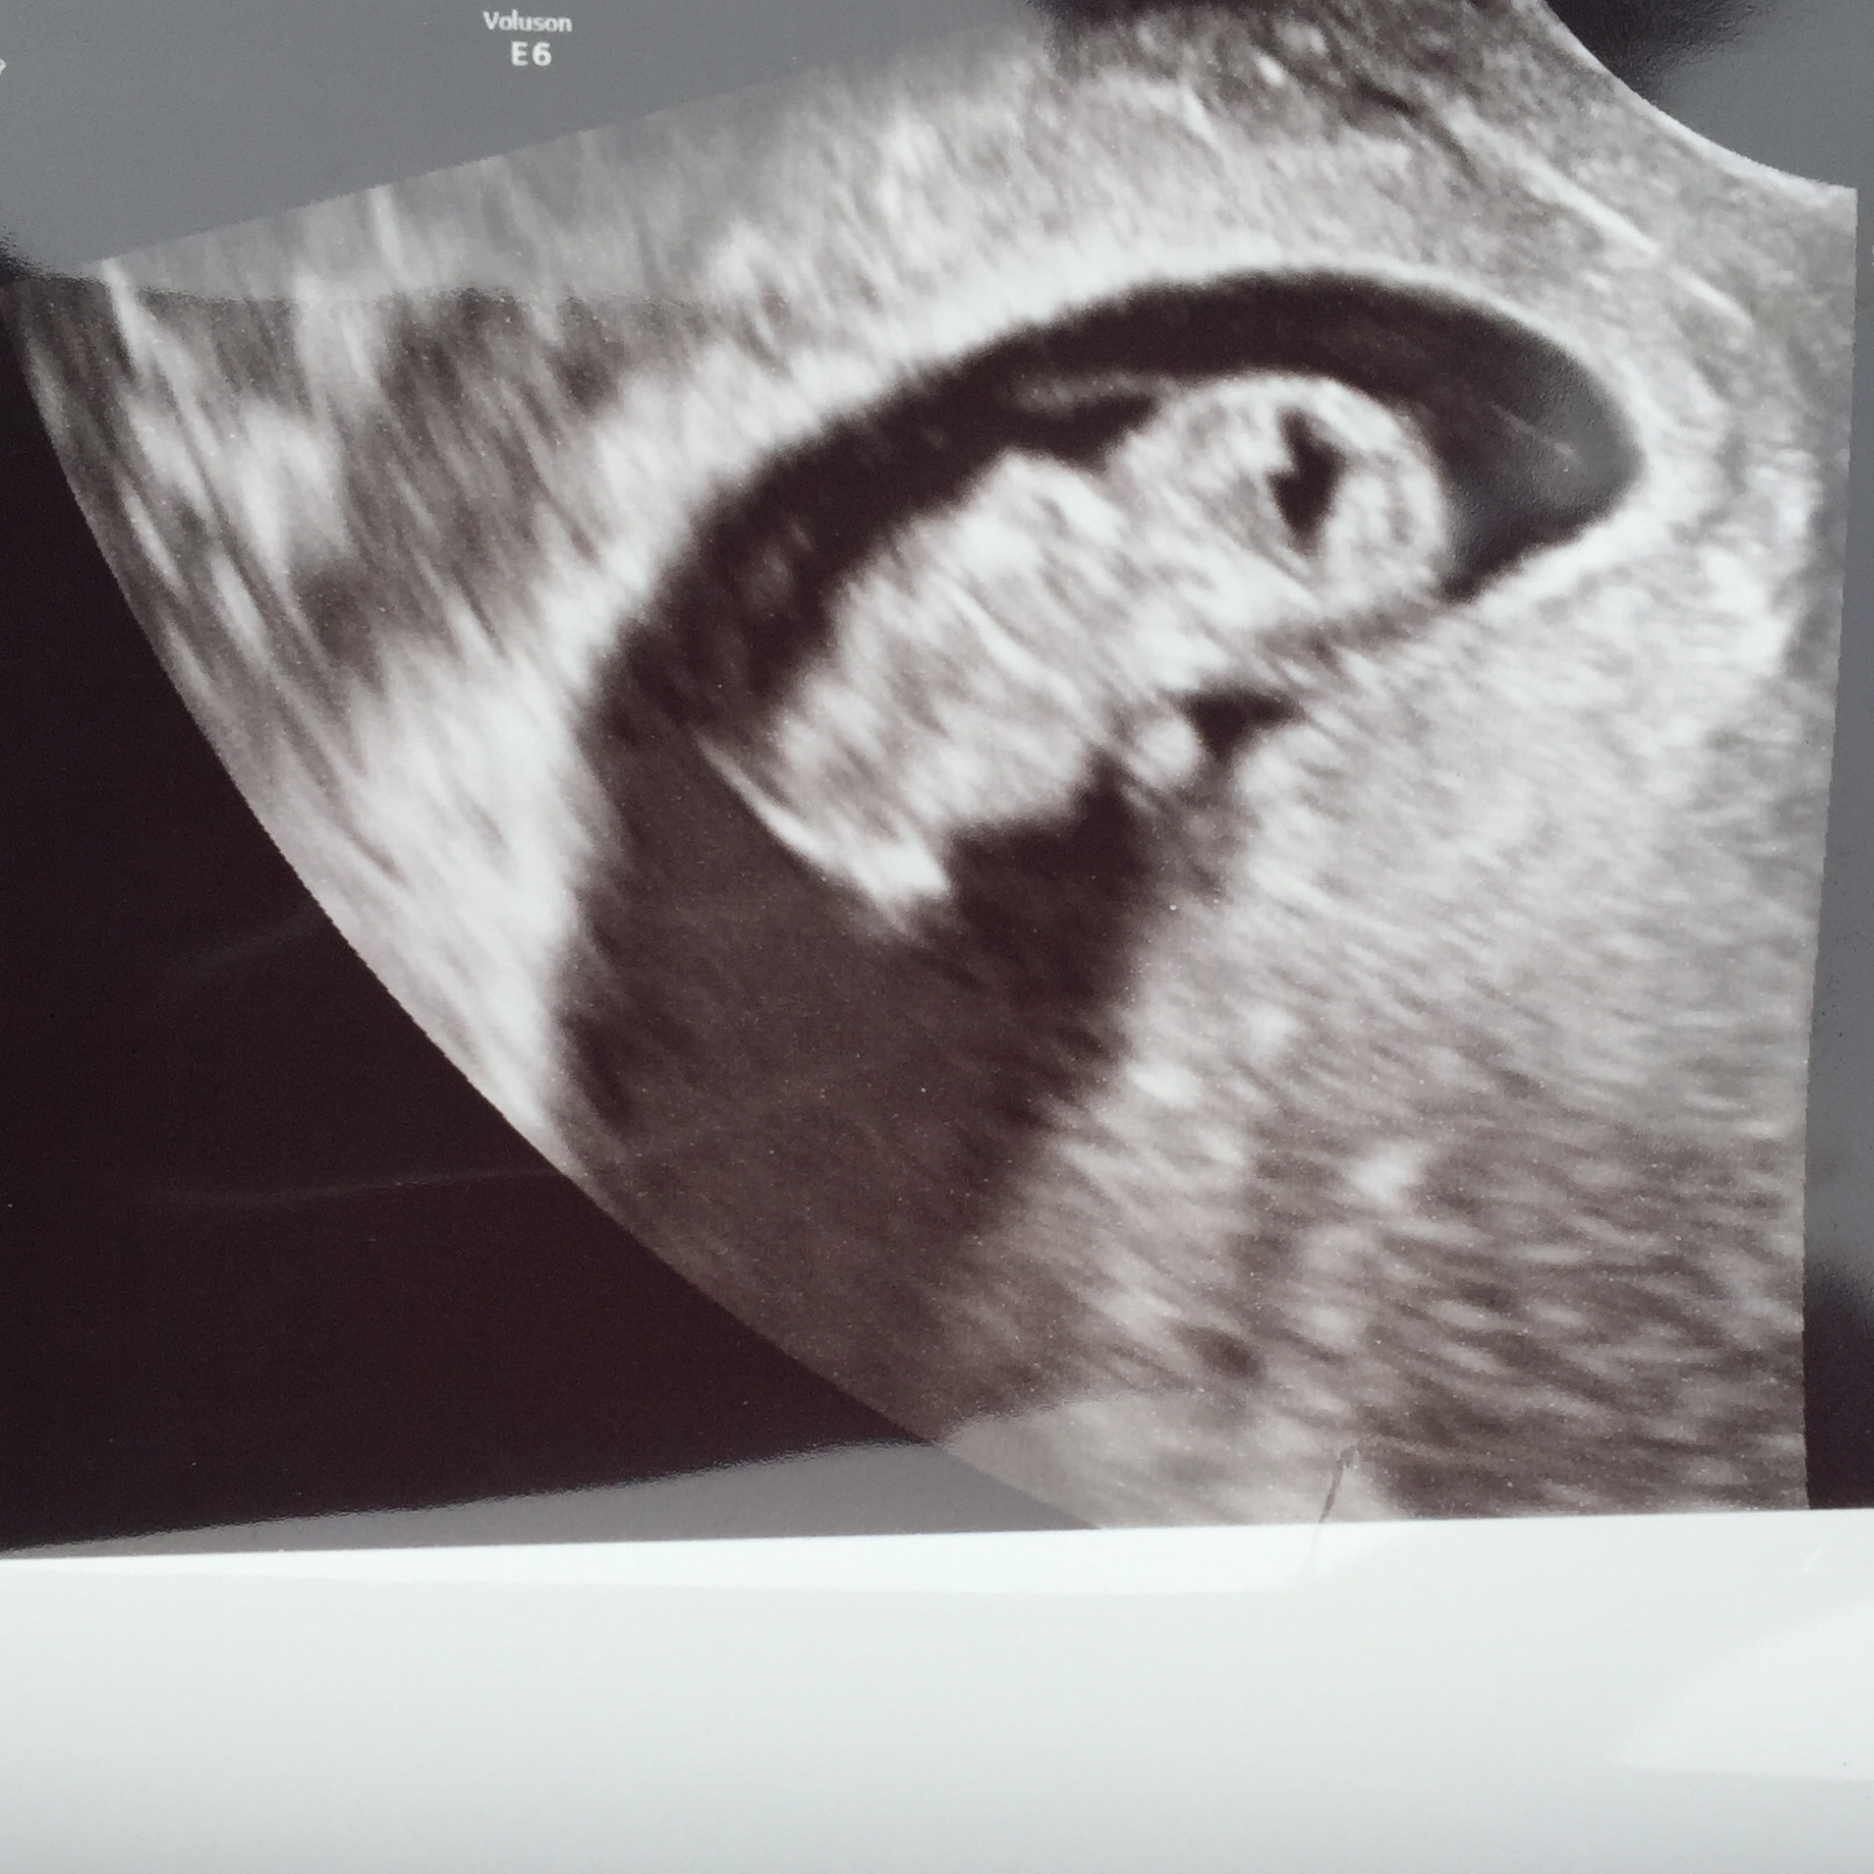

FTM! So excited to see how much my little gummy bear has grown in two weeks! 1st pic is at 6w5d, HR 147, and just a little blob with a flickering heart. 2nd & 3rd pics are at 8w5d, HR 176, and looked so much like a tiny baby with bitty arms and legs. Doc says baby is healthy and quite a dancer, it was moving and waiving all over the place. What a blessed moment to see!